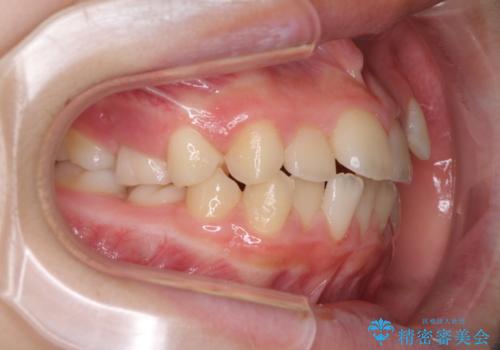

- 八重歯と乳歯が残っていることを気にして来院された患者様です。

乳歯が3歯残っており、下顎は左右ともに後続永久歯がない状態でした。

口元が突出しており、口が閉じにくかったため、乳歯を含め上下5歯を抜歯して矯正治療を行うこととしました。